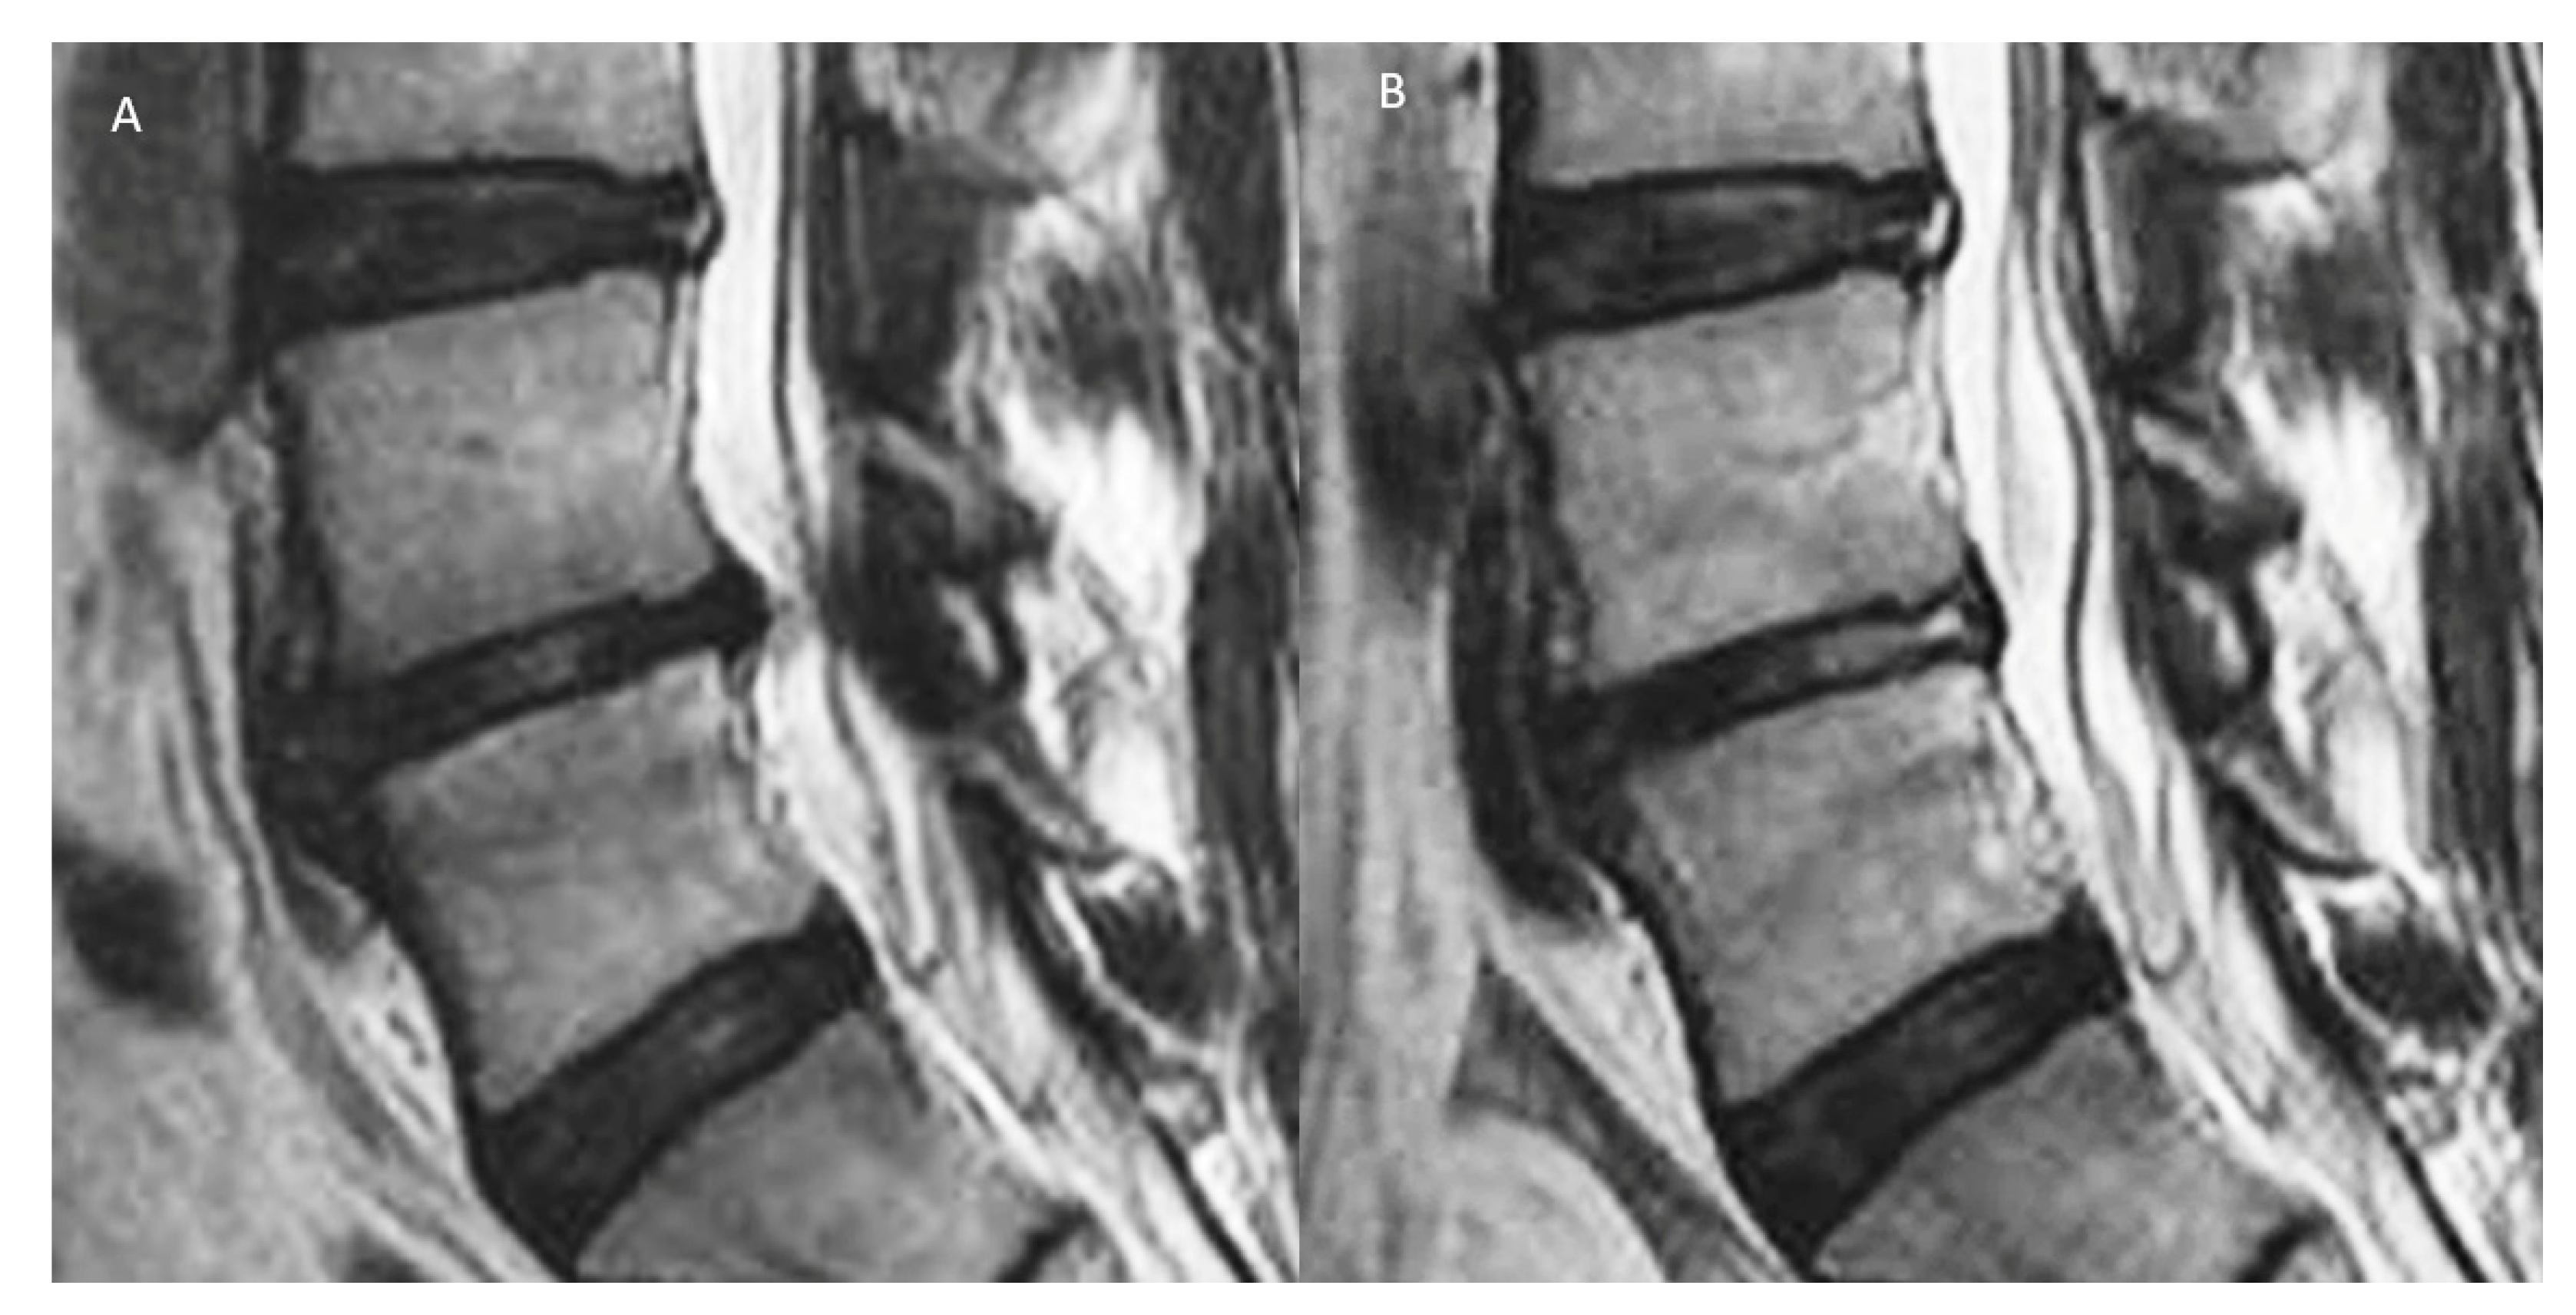

- Kim, H.S.; Adsul, N.; Yudoyono, F.; Paudel, B.; Kim, K.J.; Choi, S.H.; Kim, J.H.; Chung, S.K.; Choi, J.-H.; Jang, J.-S.; et al. Transforaminal Epiduroscopic Basivertebral Nerve Laser Ablation for Chronic Low Back Pain Associated with Modic Changes: A Preliminary Open-Label Study. Pain Res. Manag 2018, 2018, 6857983. [Google Scholar] [CrossRef] [PubMed]

- Modic, M.T.; Steinberg, P.M.; Ross, J.S.; Masaryk, T.J.; Carter, J.R. Degenerative disk disease: Assessment of changes in vertebral body marrow with MR imaging. Radiology 1988, 166, 193–199. [Google Scholar] [CrossRef]